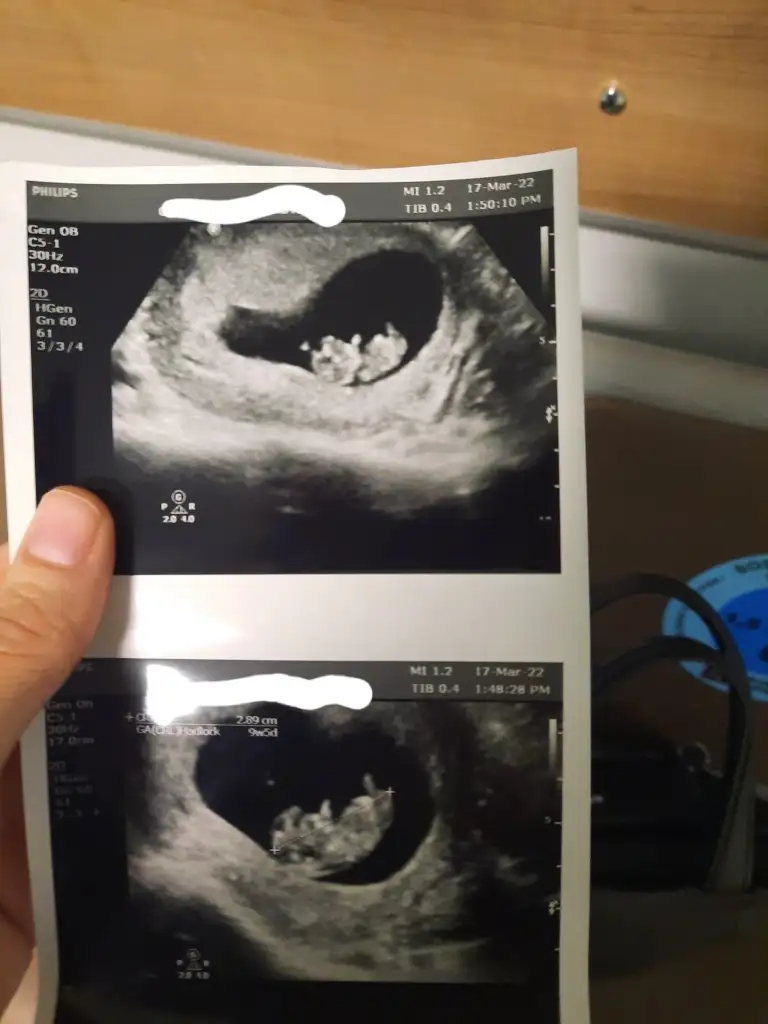

ay maşallah kuzum erkek gibi duruyorKızlar bugün yeni kağıdımızı aldık buna göre sizce nedir![]()

Doktor tahminde bulundu mi canım?Kızlar bugün yeni kağıdımızı aldık buna göre sizce nedir![]()

Bacım cinsiyet sormak için gittiğimi biliyordu. 11+4 üm baktı iyice sana net bişey söyleyemem şuan bi tahmin beklediğin için kız olduğunu söyleyebilirim ama net değil 14-16. haftanda yine görün net öğrenelim dedi.Doktor tahminde bulundu mi canım?